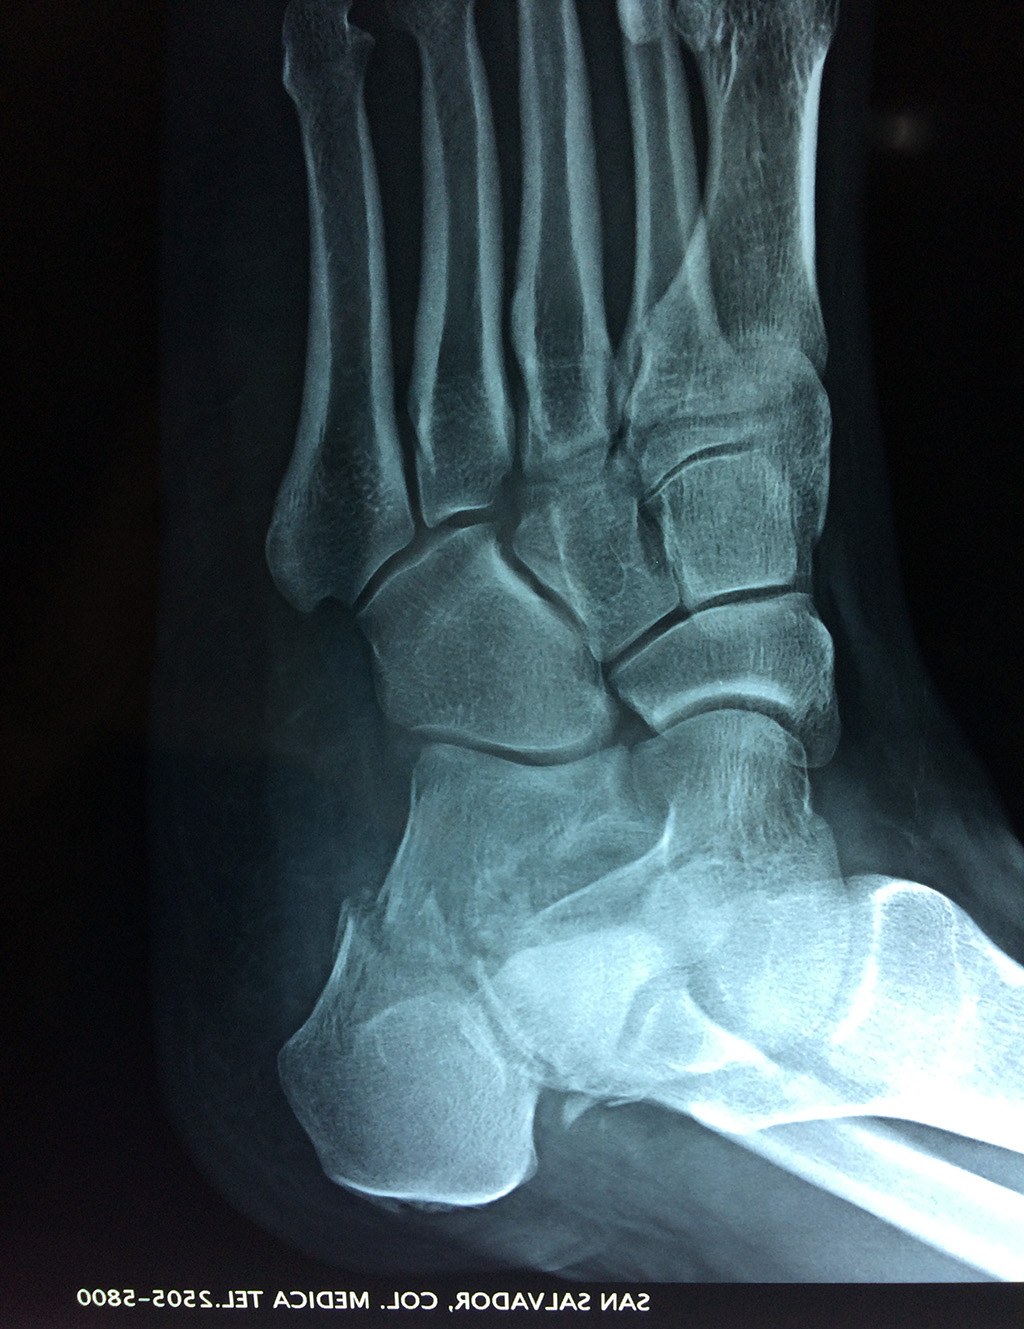

El calcáneo (del latín Os calcis) es un hueso del pie (tarso), corto, asimétrico, de forma cúbica irregular, con seis caras: superior e inferior, laterales y anterior y posterior, de las cuales dos son más o menos articulares.

Este hueso constituye el talón del pie. Se encuentra en la parte inferior de la primera fila del tarso. Se articula con el astrágalo por arriba y con el cuboides por delante. Constituye el primer punto de apoyo del pie durante la marcha, situándose en una de las zonas peor irrigadas del cuerpo y protegido plantarmente por la almohadilla plantar de tejido adiposo, con función amortiguadora.

En su cara posterior recibe la inserción del tendón más plantar, implicada en diversas enfermedades como la fascitis o el espolón calcáneo. La posición del calcáneo en relación al astrágalo (articulación subastragalina) y al suelo determinan la posición de retropié en varo, en valgo o neutra.

Los retropiés varos y sobre todo, los retropiés valgos, son responsables de distintas enfermedades del aparato locomotor y contribuyen a que aparezcan alteraciones de la marcha normal fisiológica, con consecuencias clínicas importantes (dolor, sobrecargas, aplanamiento, fatiga muscular, juanetes, etc.) tanto a nivel de pie como a nivel del miembro inferior.